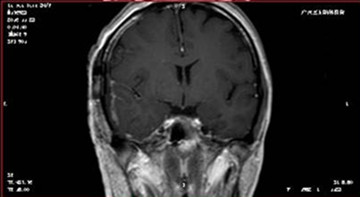

患者影像学资料:

▲术后MRI